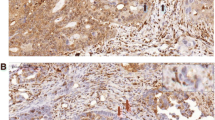

Immunohistochemical staining was carried out on TMAs using the PTEN monoclonal antibody 6H2.1 (Dako, Glostrup, Denmark) that has been used previously [34–36]. Essentially, tissue sections (3 μm) as TMAs were deparaffinised by heating the slides at 55-60°C for 2 hours, then soaking in xylene and hydrating by passing through a graded series of ethanol to water. Antigen retrieval was carried out by microwaving the slides in target retrieval solution pH 9 (DAKO). Endogenous peroxidase was quenched by incubating the slides in Peroxidazed I reagent (Biocare Medical, Concord, CA) for 5 min and background staining was blocked by incubation in Background Sniper reagent (Biocare Medical). Slides were stained using a 1:100 dilution of PTEN primary antibody 6H2.1 and detected using the MACH 3™ mouse HRP polymer detection system according to the manufacturer’s protocol (Biocare Medical). Slides were counterstained in methyl green (Sigma). The TMAs contained 3 sections taken from the same core. Each section was assessed by 2 blinded pathologists (JC and AR) and a majority score was determined for each pathologist (3 IHC readings). PTEN staining was mostly cytoplasmic. Intensity was scored on a four-tier system: 0, no staining; 1, weak; 2, moderate; and 3, strong. Loss of PTEN was defined as majority score 0 (Figure 2). The pathologist’s majority scores were compared directly for an IHC concordance rate. Specimens concordant on IHC were used for IHC versus TaqMan concordance rate.